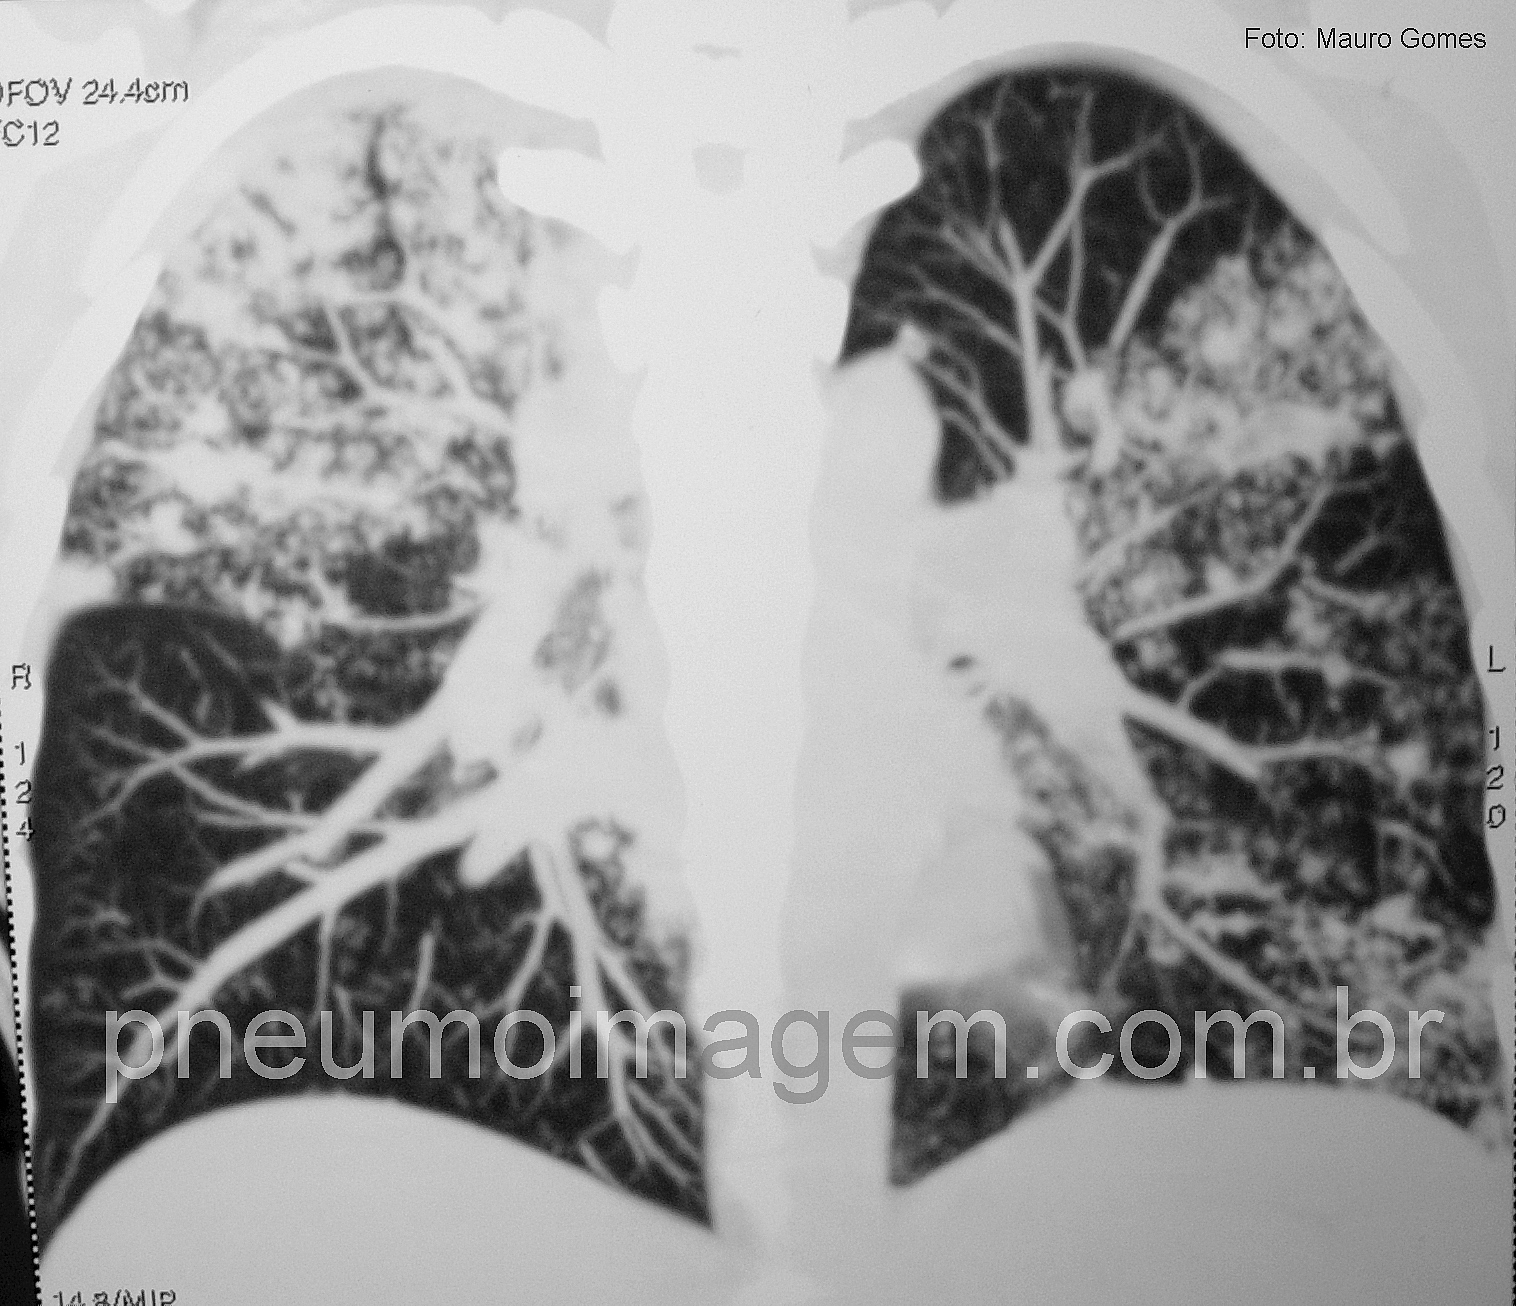

Novos e intensos esforços foram desenvolvidos nos últimos anos para melhorar a busca de casos de tuberculose (TB), o que trouxe maior preocupação com a epidemia, pois os dados revelaram que há quase meio milhão a mais de casos da doença do que o estimado anteriormente pela Organização Mundial da Saúde (OMS).

O problema da TB multirresistente (MDR-TB) continua e essa forma da doença já foi relatada em 100 países. Em todo o mundo, cerca de 3,5% de todas as pessoas que desenvolveram TB apresentaram a forma MDR-TB. Em 2013, foram detectados 136 mil casos de MDR-TB, contra 52.825 em 2009 e 97.000 pessoas iniciaram o tratamento, ante 30.500 em 2009. Alguns países têm graves epidemias de MDR-TB e as taxas de sucesso do tratamento são baixas, aponta o relatório.